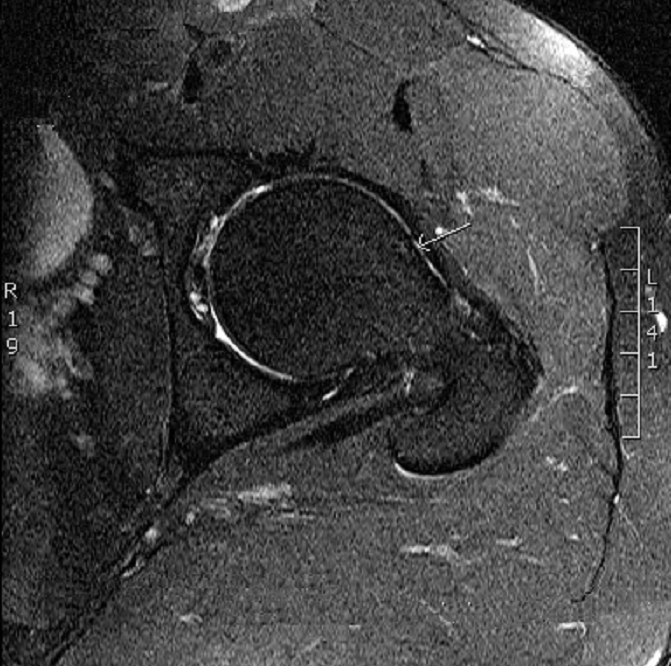

En la artroresonancia magnética se observó: en la cadera izquierda un fémur tipo CAM, con ruptura del labrum anterosuperior y quiste intralabral. Lesión condral superior, con pequeños pits en transición cabeza-cuello (ver Figura 1 y Figura 2).

RMN: permite identificar el estado del cartílago articular y del labrum. La artrografía por RMN es el examen de elección porque delinea mejor los fragmentos del labrum y sutiles lesiones del cartílago, ya que el medio de contraste intraarticular distiende las partes de la articulación y permite una mejor visualización de sus estructuras10, 18. Este método fue el utilizado para confirmar el diagnóstico del paciente al evidenciar el daño articular.